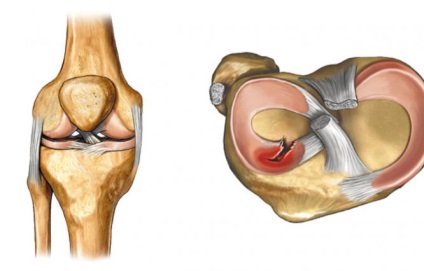

Meniscului este un strat de cartilaj în cavitatea articulației genunchiului, care servește ca amortizare și stabilizare. Astfel de straturi în genunchi două - interne și externe. ruptură de menisc apare de obicei din cauza.

Menisc - o formațiune flexibilă de țesut fibro cartilaginos în formă de semilună. În structura sa, meniscul este aproape de tendonul. În genunchi există două: externe și interne. Acestea sunt situate pe suprafata.

Conform structurii sale articulația genunchiului este complexă, pentru că, în plus față de numeroase componente constă din meniscului. Aceste elemente sunt necesare pentru a separa cavitatea articular în două părți. În timpul mișcărilor.

Se numește strat cartilaj meniscului articulației genunchiului, care se află între suprafețele de tibie și femur. Meniscului actioneaza ca un amortizor de șocuri și stabilizator. Dar o parte din presiune, în special în sport.